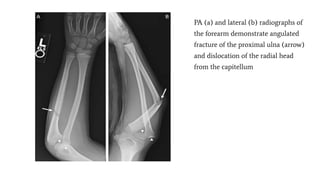

PA (a) and lateral (b) radiographs of

the forearm demonstrate angulated

fracture of the proximal ulna (arrow)

and dislocation of the radial head

from the capitellum

Radiocapitellar Relation;

A line drawn along the long axis

of radius bisects the capitellum

regardless of the degree of

flexion or extension.